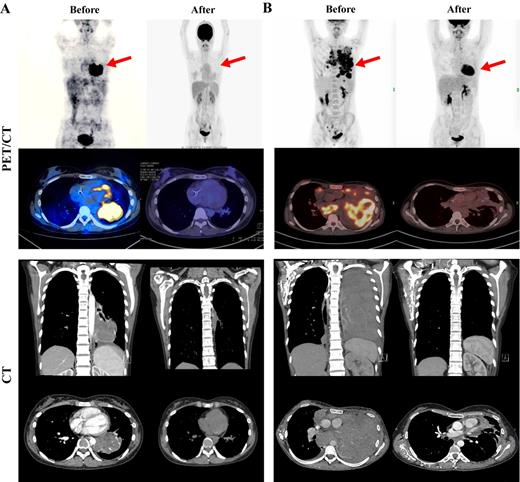

Results: Both HL patients relapsed after multi-line chemotherapies and radiotherapy. One patient relapsed after autologous hematopoietic stem cell transplantation. The main manifestations were cough and dyspnea caused by large lung masses. Both patients received 3 kinds of PD-1 blockade. One progressed after stopping Nivolumab and enrolled the clinical trial of decitabine and Camrelizumab for 6 courses and got stable disease(SD), then changed to Camrelizumab combined with ICE for 4 cycles and obtain complete metabolic remission(CMR). The other patient progressed with Nivolumab or Camrelizumab combined with A (B) VD regimen, and 2 courses of BV. She was then treated with Sintilimab combined with ICE for 4 cycles and obtain CMR. Both patients' cough and dyspnea were significantly improved, and lung lesions were significantly reduced after receiving 1 cycle of PD-1 blockade with ICE regimen and the quality of life was greatly improved. After 4 courses of treatment, the PET/CT assessment achieved CMR. The main side effect was a second-degree bone marrow suppression and can be tolerable for the patient.

Conclusion: PD-1 blockade combined with ICE regimen chemotherapy has significant curative effect and mild adverse reactions, can be used to treat cases of relapsed or refractory classic HL with bulky lung involvement resistant to PD-1 blockade.